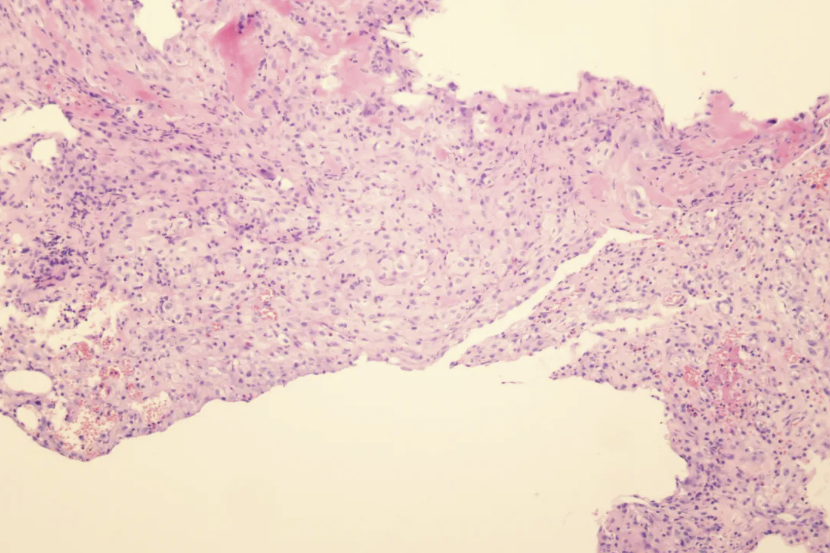

11月5日胸腔镜检查:胸腔镜进入左侧胸膜腔后吸引出约160ml淡黄色胸水,胸膜暴露后可见肺组织与前后壁层胸膜部分粘连,前后壁层胸膜大量弥漫性细小结节(图3),共活检胸膜15块送检病理,提示(左侧壁层胸膜胸腔镜活检)(图4)胸膜纤维素性渗出伴组织浸润,嗜酸性粒细胞增多及间皮增生,免疫组化结果:CK(+),CAM5.2(+),CD68(+背景),S100(-),Vimentin(+),Ki-67(+20%),TFE-3(+弱),CR(+部分),MC(+散在少量),EMA(-),CD163(+)。

图4 病理 HE染色 X100 倍 胸膜纤维素性渗出伴组织浸润,嗜酸性粒细胞增多及间皮增生